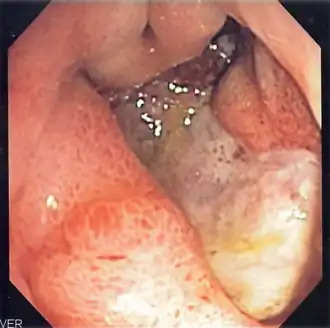

Изображение язвы желудка, полученное с помощью эндоскопа

Наиболее информативным в диагностике язвенной болезни желудка и 12-перстной кишки является эндоскопическое исследование, которое визуально подтверждает наличие язвенного дефекта, позволяет уточнить его локализацию, глубину, форму, размеры, позволяет оценить состояние дна и краев язвы, выявить сопутствующие изменения слизистой оболочки. При проведении эндоскопического исследования имеется возможность произвести прицельную биопсию — «отщипывание» кусочка ткани из краев или дна язвенного дефекта посредством специального инструментария. Полученный таким образом биоптат (кусочек ткани) направляется на гистологическое исследование, которое позволяет выявить возможную раковую природу обнаруженного язвенного дефекта (язвенная форма рака желудка).